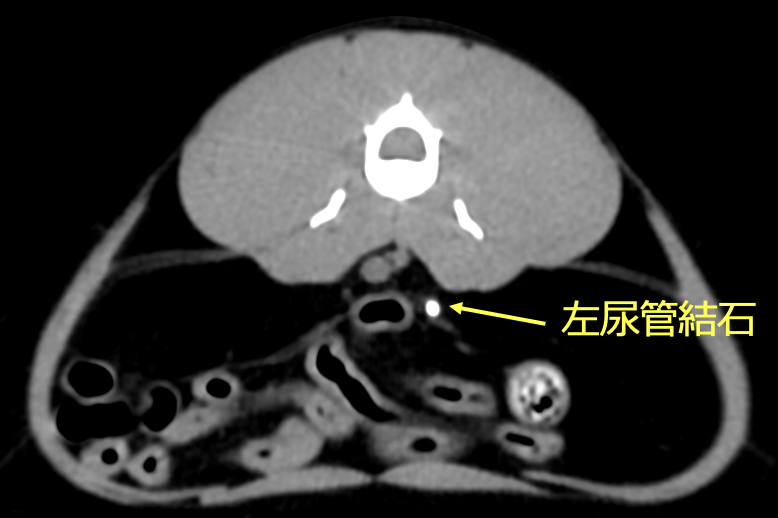

レントゲン、CT検査より左右の尿管に結石が認められた。また左腎臓腎盂の拡張が認められた。

左右尿管結石と診断した。治療は、腎臓の数値を下げるため、まずは腎瘻チューブを設置した。腎数値に改善が認められないので、開腹にて尿管膀胱側側吻合術を行った。